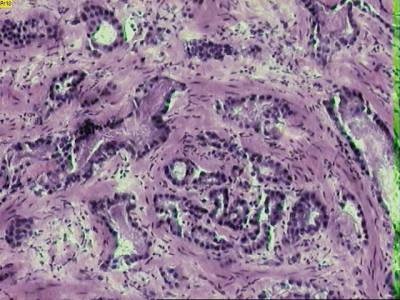

Adenocarcinoma de próstata. (Foto: DICYT)